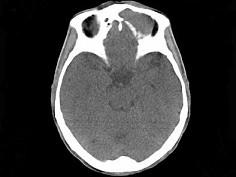

问题 男,53岁,近两年来渐进性头痛,伴左眼球外突,并向前下方移位,CT检查如图,最可能诊断为 ( )

选项 A、眶内炎性假瘤 B、眼格氏病 C、左额窦癌 D、左额窦黏液囊肿 E、额窦炎症

答案 D